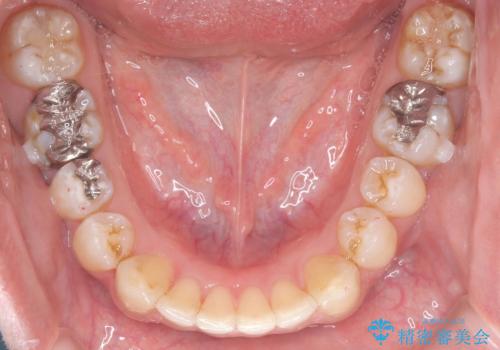

歯の隙間とデコボコ、シザーズバイトも改善され、咬み合わせや見た目が整い、患者様にも大変ご満足いただけました。